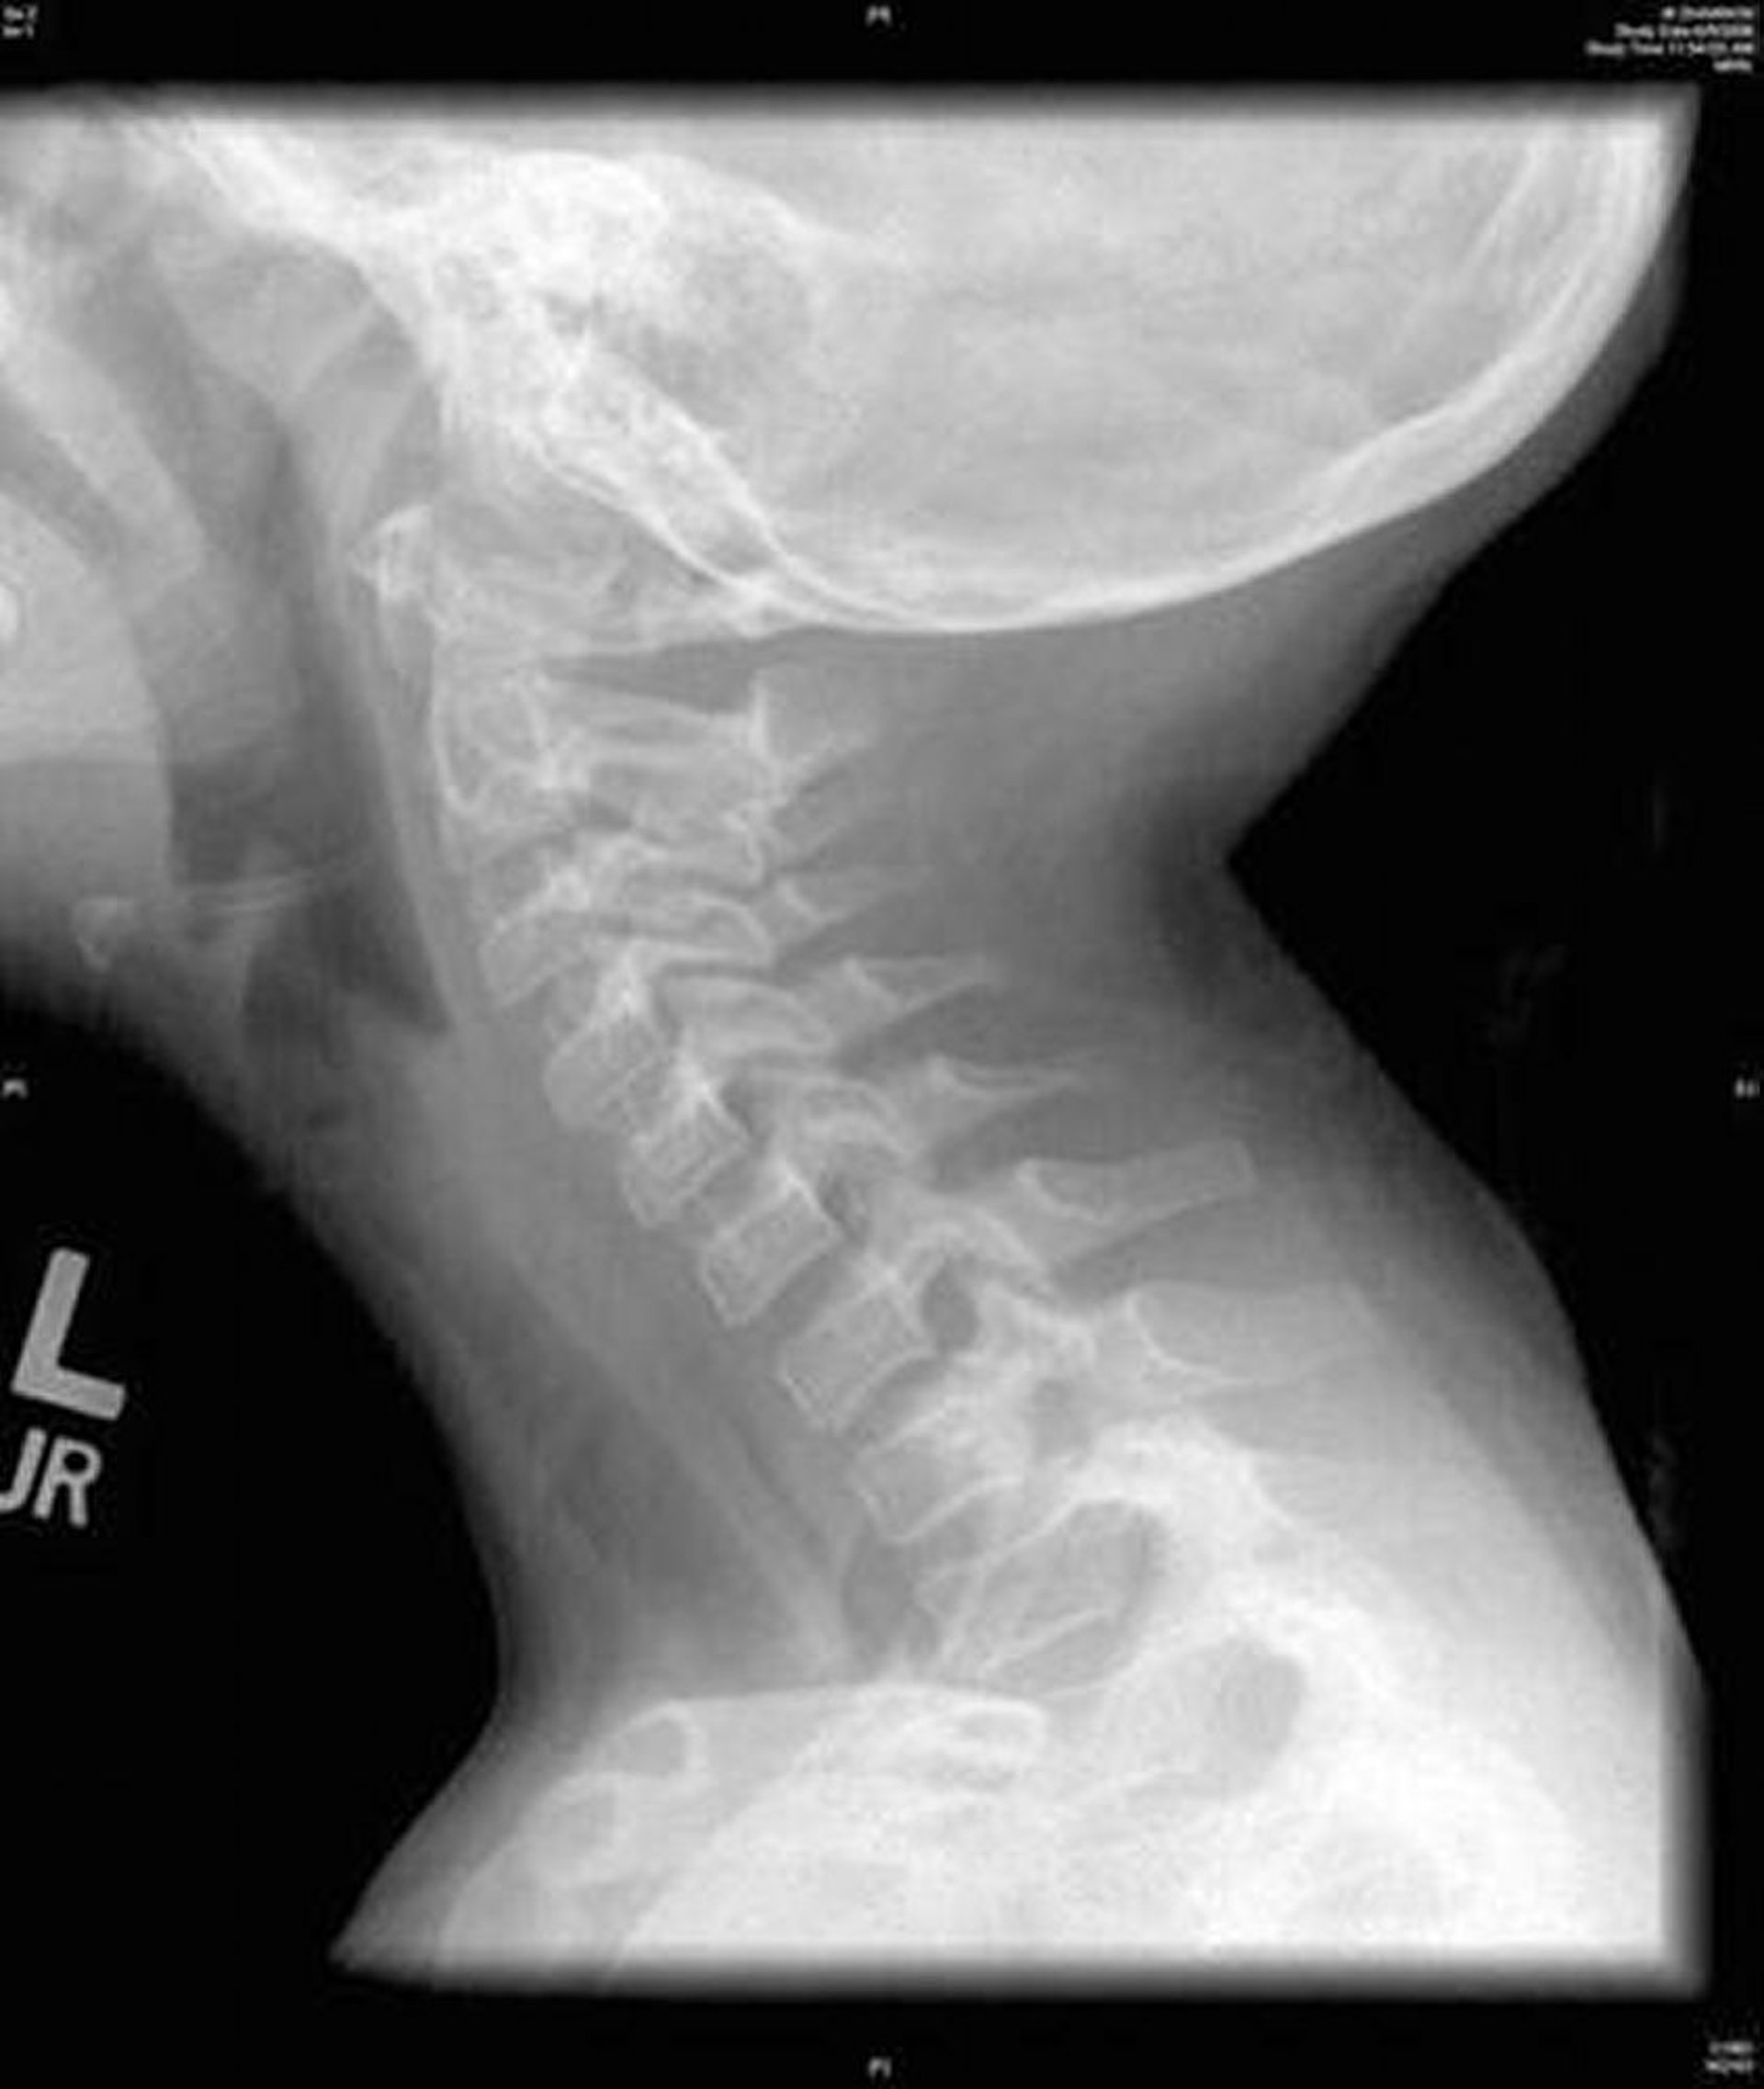

Trachéite bactérienne (Rx)

Cette image montre une radiographie de profil du cou qui présente une irrégularité diffuse de la trachée caractéristique d'une trachéite bactérienne.